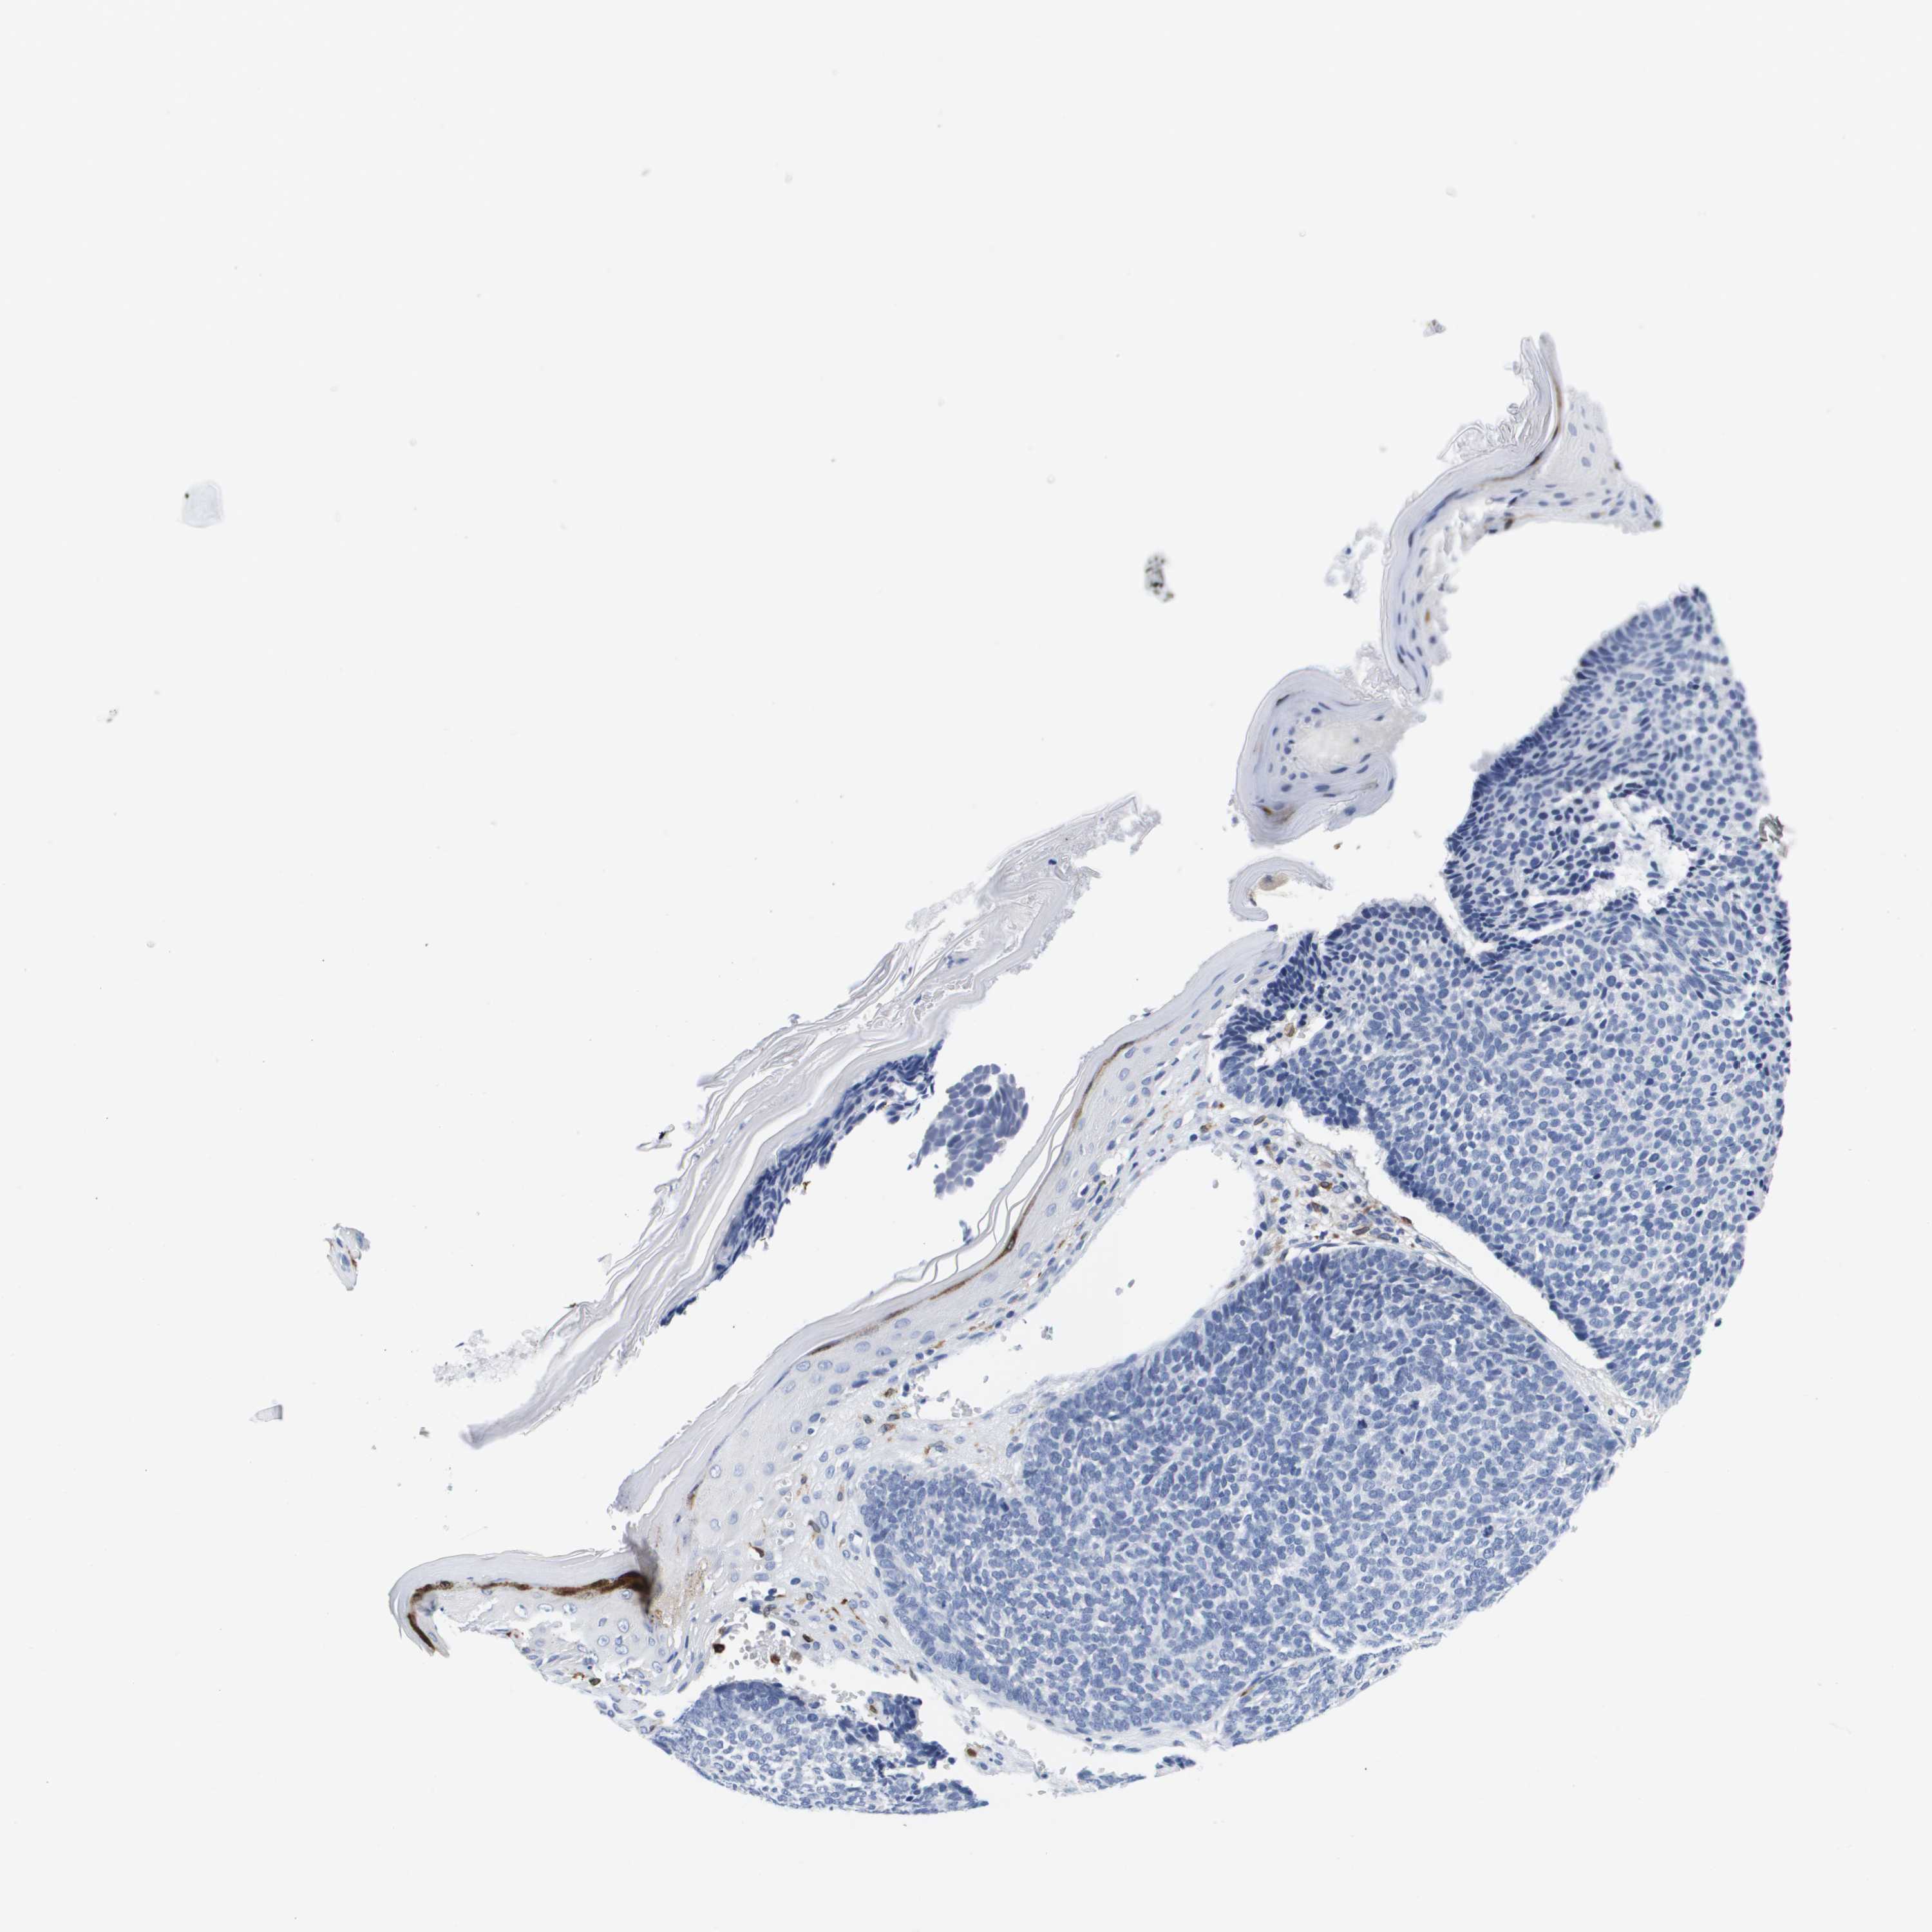

SKIN CANCER - Protein expressioni

A mouse-over function shows sample information and annotation data. Click on an image to view it in a full screen mode. Samples can be filtered based on level of antibody staining by selecting one or several of the following categories: high, medium, low and not detected. The assay and annotation is described here.

Antibody staining in the annotated cell types in the current human tissue is reported as not detected, low, medium, or high, based on conventional immunohistochemistry profiling in selected tissues. This score is based on the combination of the staining intensity and fraction of stained cells.

Each image is clickable and will lead to virtual microscopy that enables deeper exploration of all samples and also displays staining intensity scores, fraction scores and subcellular localization as well as patient and tissue information for each sample.

Antibody CAB017444

Staining

Medium

Intensity

Moderate

Quantity

75%-25%

Location

Cytoplasmic/membranous

Squamous cell carcinoma, NOS